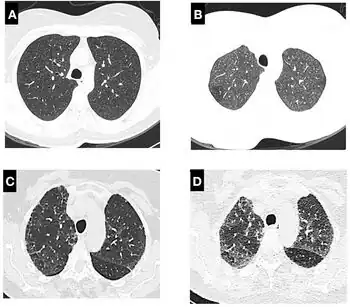

a-d)High-resolution computed tomography scan in individual with Hypersensitivity Pneumonitis (non-fibrotic)

A chest X-ray or CT is necessary to differentiate between pneumonitis and pneumonia of an infectious etiology. Some degree of pulmonary fibrosis may be evident in a CT which is indicative of chronic pulmonary inflammatory processes. Diagnosis of Pneumonitis is often difficult as it depends on a high degree of clinical suspicion when evaluating a patient with a recent onset of a possible interstitial lung disease. In addition, interpreting pathologic and radiographic test results remains a challenge to clinicians. Pneumonitis is often difficult to recognize and discern from other interstitial lung diseases.[7]

Clinical tests include chest radiography or (HRCT) which may show centrilobular nodular and ground-glass opacities with air-trapping in the middle and upper lobes of the lungs. Fibrosis may also be evident. Bronchoalveolar Lavage (BAL) findings coinciding with pneumonitis typically include a lymphocytosis with a low CD4:CD8 ratio.[7][12]

Reticular or linear patterns may be observed in diagnostic imaging.[7] Pneumonitis may cause subpleural honeycombing, changing the shape of the air spaces in an image, which may be used to identify the respiratory disease.[7] The interlobular septa may also thicken and indicate pneumonitis when viewed on a scan.[7]